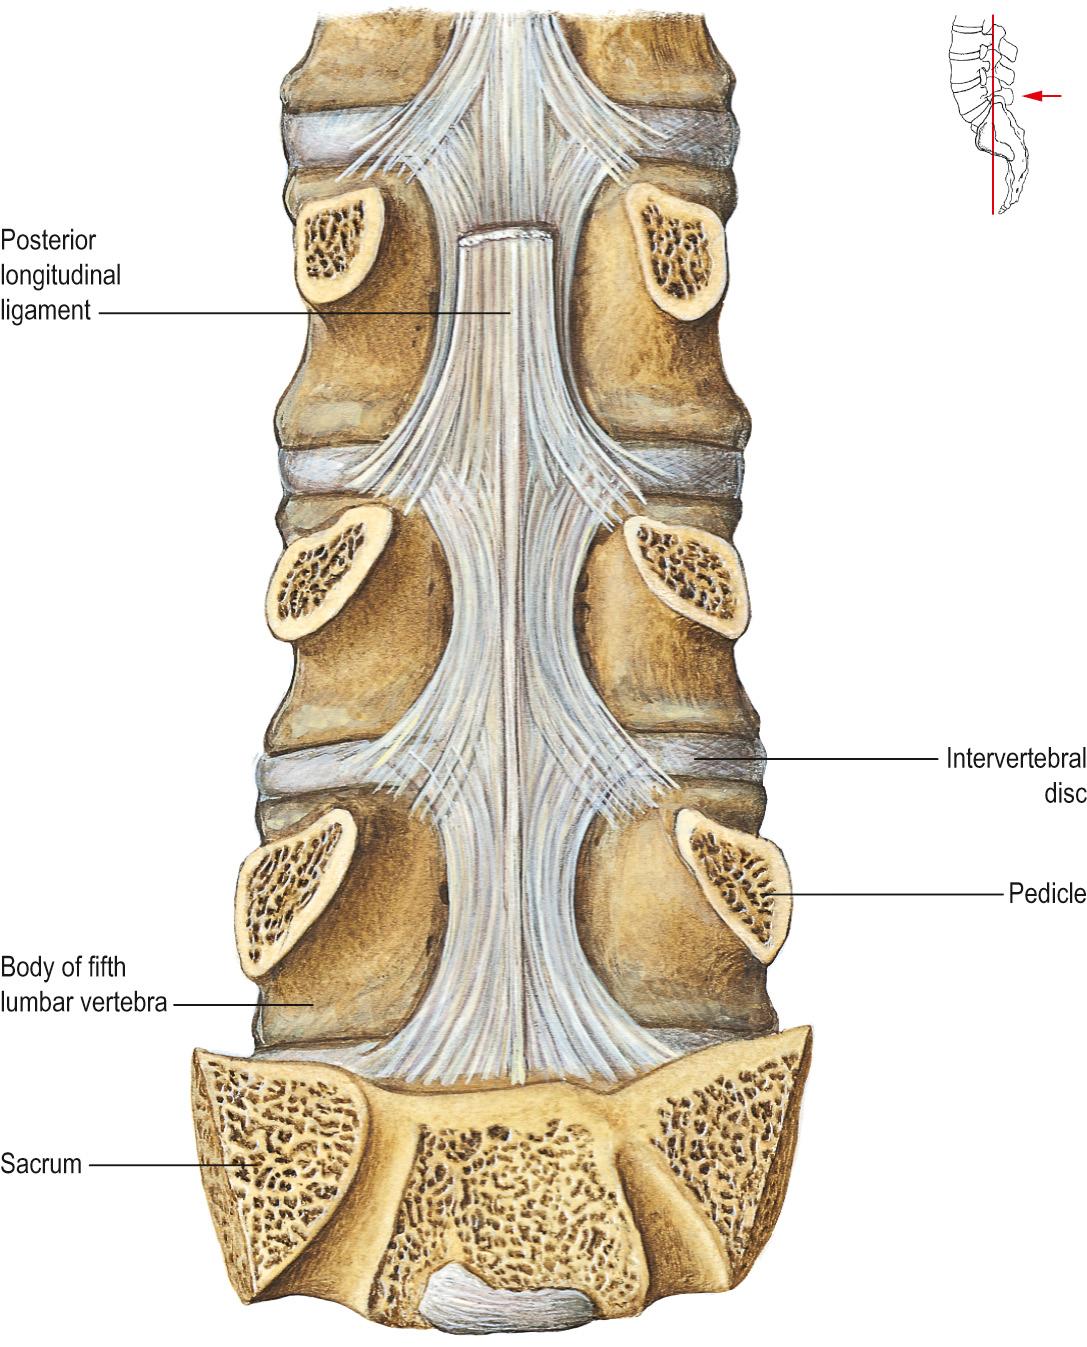

DOCS - The interspinous ligament is located between the spinous processes of adjacent vertebrae in the spine. It extends from the base of one spinous process to the apex of the next,

Anatomy of the vertebral column and spinal cord (Chapter 55) - Essential Clinical Anesthesia Review